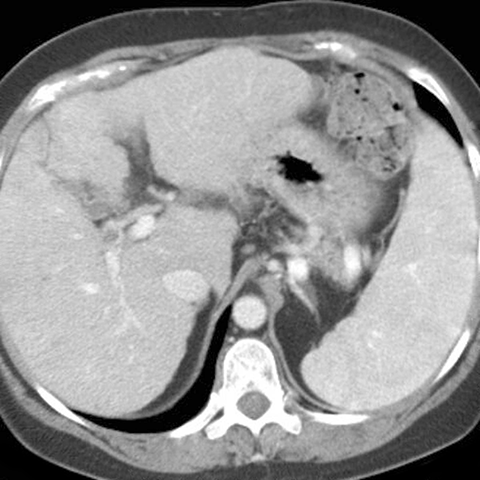

Heterogeneous Splenic Enhancement [2 of 2]